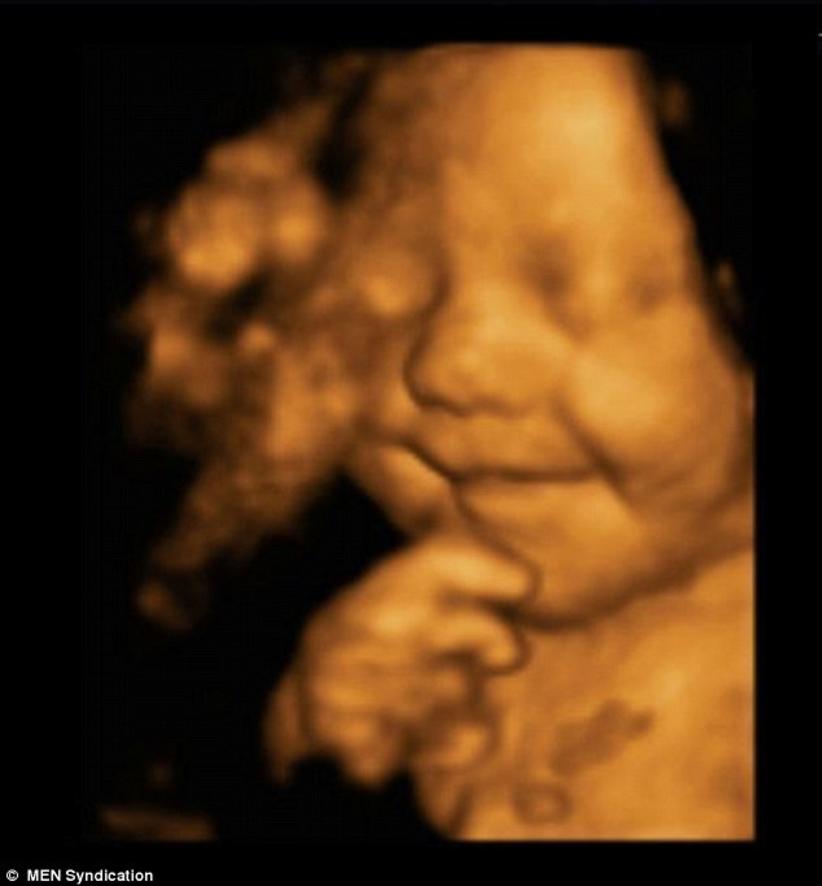

A felicidade contagiante é do pequeno Leo Hargreaves que já ganhou uma série de admiradores pelo seu sorriso ainda na barriga da mãe.

Uma ultrassom feita com 31 semanas revelou que ele tinha um enorme sorriso no rosto através da digitalização.

A imagem é um ultrassom em 4D, cada vez mais popular entre os futuros pais, que desejam ver como está a criança na barriga da mãe.